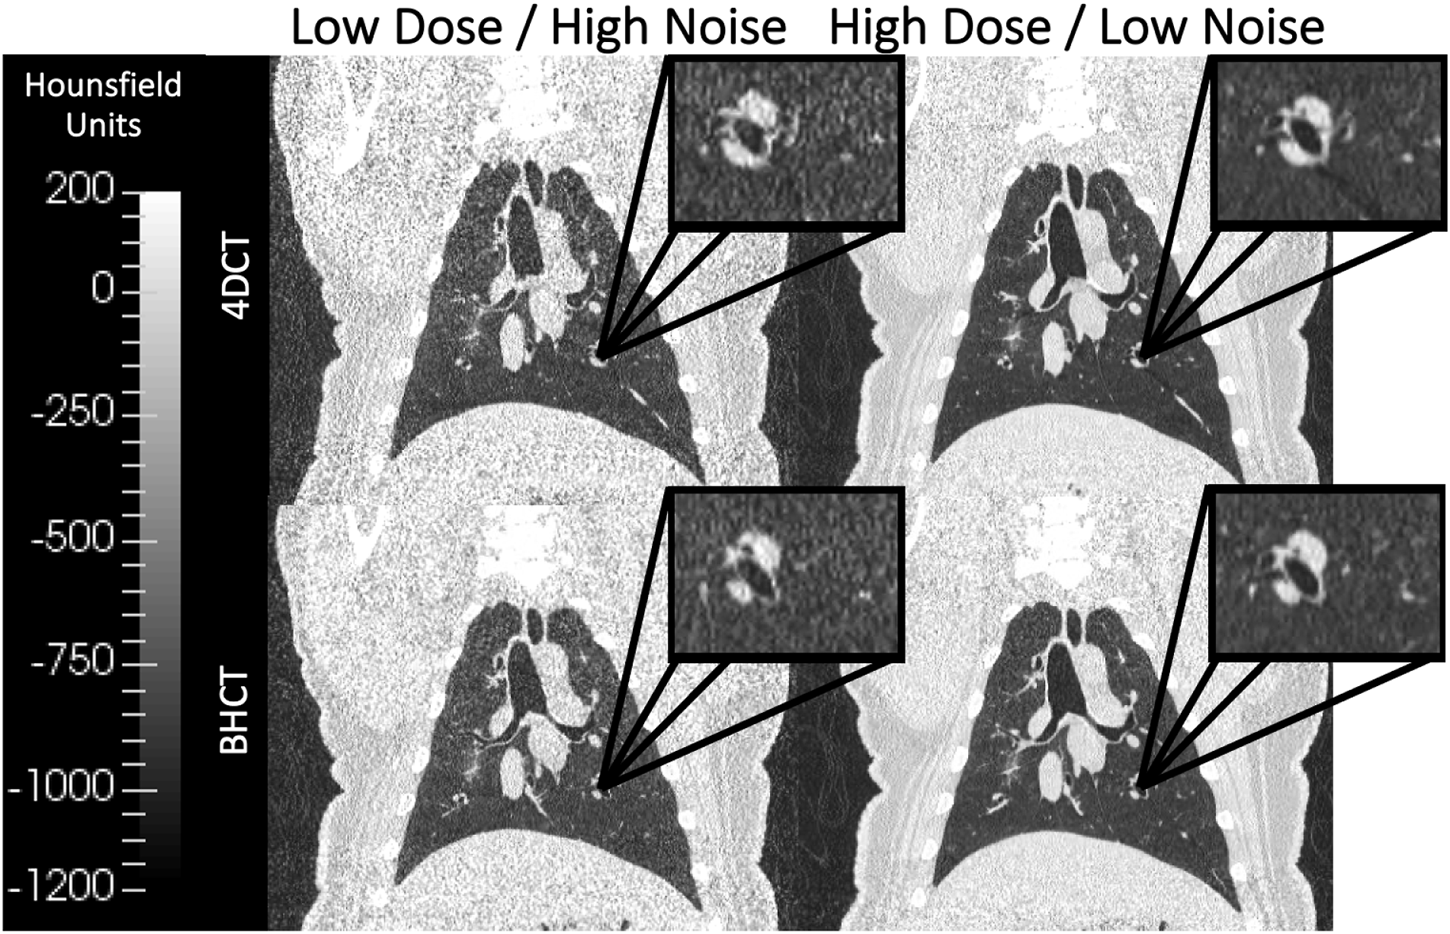

For all subjects on each of the two scan dates, repeated 4DCT and BHCT scans with different levels of image noise were acquired of each subject. Two consecutive 4DCTs were acquired; the first 4DCT was acquired using 100 mAs and the second 4DCT was acquired with 10 mAs, as shown in the top row of Figure 2. During 4DCT acquisitions, subjects were ventilated at 15 breaths per minute (BPM) with a 1,000 cubic centimeter (cc) tidal volume (TV). The Varian Real-Time Position Management (RPM) system (Varian Medical Systems, Inc., Palo Alto, CA) was used to track subjects’ chest positions during 4DCT acquisitions. RPM respiratory traces were used to reconstruct 4DCT image data into 10 breathing phases classified by their inspiratory (IN) or expiratory (EX) percentage (0EX, 20IN, 40IN, 60IN, 80IN, 100IN, 80EX, 60EX, 40EX, 20EX), as previously described (Han et al., 2011).

FIGURE 2

Coronal images of scans acquired at multiple dose levels are shown. The top row shows 4DCTs acquired with low dose (CTDIvol = 6.07 mGy) on the left and high dose (CTDIvol = 60.7 mGy) on the right. Similarly, the bottom row shows 4DCTs acquired with low dose (CTDIvol = 1.3 mGy) on the left and high dose (CTDIvol = 7.9 mGy) on the right. Qualitatively, the lower dose images in the left column show increased image noise relative to the high dose images of the right column. All four displayed images were reconstructed without IR applied.

BHCTs were also acquired on each scan date at 10 intermediate mAs levels (ranging from equivalent noise to 15–100 mAs 4DCTs). Coronal BHCT images acquired with highest (equivalent to 15 mAs4D) and lowest (equivalent to 100 mAs4D) noise levels are shown in the bottom row of Figure 2. BHCT scans were acquired at three distinct lung volumes: maximum expiration (MEBH), maximum inspiration (MIBH) and 80% inspiration (80%Insp) which are analogous to 4DCT 0EX, 100IN and 80IN, respectively. The two different inspiratory volumes (80%Insp and MIBH) were imaged to allow multiple TV options to facilitate equivalent TV (ETV) matching since Jacobian ventilation values are volume dependent (Du et al., 2013). For each of the three BH volumes, the subject held constant pressure to maintain the volume while alternating craniocaudal and caudocranial scans were acquired with decreasing mAs values. This BHCT image acquisition method has been previously described in detail (Flakus et al., 2020). Scans were always acquired in order from highest to lowest dose. All scans were reconstructed with the same parameters used for phantom scans, including both with and without SAFIRE3 IR. Figure 3 shows an example 10 mAs 4DCT reconstructed with and without IR applied for noise reduction.